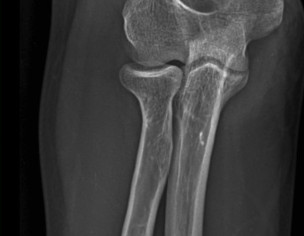

My husband had elbow surgery on 9th of August. I want to know about physiotherapy. When can we start physiotherapy so he can bend and extend his arm freely.Kindly guide us. If we start now will it effect joint or not. TIA

Attach Photo here: